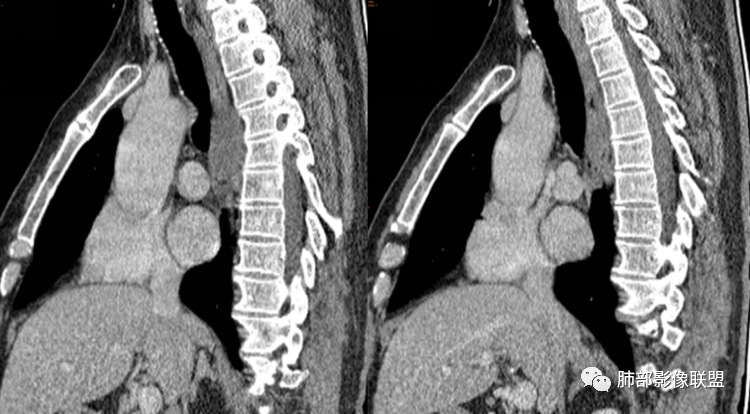

患者,男,43岁,无意间发现纵隔肿物,无胸闷胸痛,无心慌气短,无咳嗽,无吞咽困难等不适。体检发现的,无症状。

气管、左主支气管后方,食道左侧囊性占位,壁薄且均匀、光滑。气管及左主支气管受压凹陷、变形。

食道也受压变形、移位。

气管后,食道侧后方,最大病灶在脊柱前。